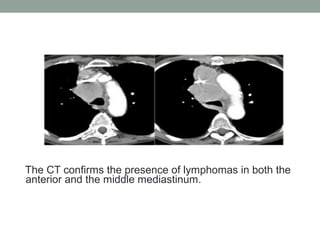

The CT confirms the presence of lymphomas in both the

anterior and the middle mediastinum.